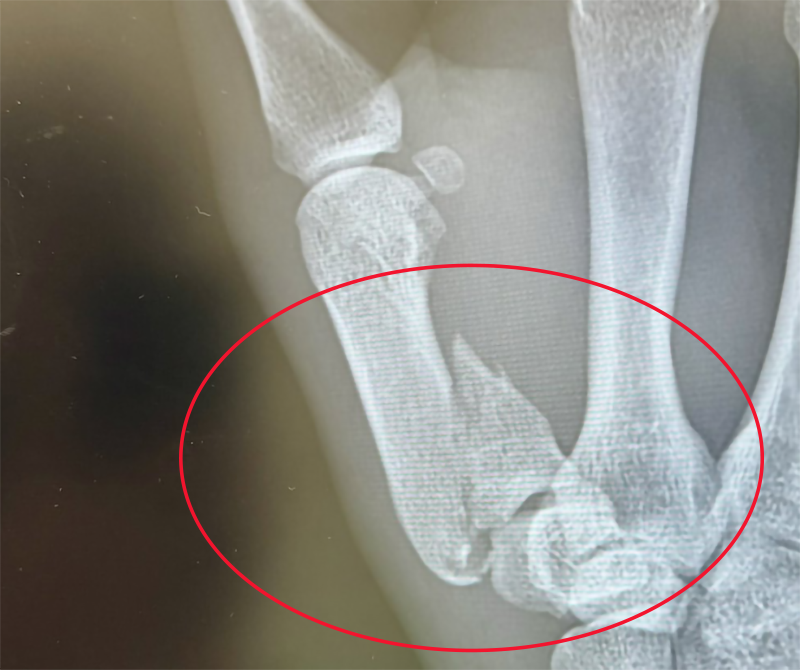

右手親指が骨折!太田のXより